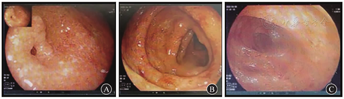

患者男,44岁,主因"间断腹泻、便血6个月余"于2020年9月18日就诊于空军军医大学西京医院消化内科。既往史:患者2010年被确诊为过敏性紫癜性肾炎,2015年确诊为慢性肾衰竭、原发性高血压,2016年10月22日行同种异体ABO血型相容性肾移植术,术后长期服用他克莫司(9:30口服,1.5 mg/次;21:30口服,1.0 mg/次)、咪唑立宾(50 mg/次,2次/d,与他克莫司同时服用)、泼尼松(早餐后口服,5 mg/次,1次/d)抗排斥反应治疗,病情平稳;规律服用坎地沙坦酯(8 mg/次,1次/d)降血压治疗1年,血压控制良好。个人史和家族史无特殊。2020年4月,患者无明显诱因出现腹泻,每日排便10余次,黏液脓血便,伴腹痛,以左下腹为主,便后腹痛可部分缓解。遂于当地医院就诊,实验室检查示白细胞计数为12.78×109/L,超敏C反应蛋白为12.1 mg/L;粪便隐血试验阳性;巨细胞病毒(cytomegalovirus,CMV)、EB病毒阳性;肝肾功能、红细胞沉降率(erythrocyte sedimentation rate,ESR)均未见异常;结核感染T细胞斑点试验(tuberculosis infection T cell spot test,T-SPOT)、艰难梭菌、粪便细菌培养均为阴性。2020年4月10日,患者肠镜检查(图1)示全结肠和直肠黏膜弥漫性充血、水肿,局部可见多发糜烂和浅溃疡灶,部分为深凹溃疡,表面附脓苔,考虑UC可能,病理检查示肠黏膜慢性活动性炎伴糜烂,部分隐窝不规则,可见分支,杯状细胞减少,部分表面上皮不规则,间质大量淋巴细胞、浆细胞,中等量中性粒细胞,少量嗜酸性粒细胞浸润,伴隐窝炎和隐窝微脓肿,局部淋巴滤泡形成,抗酸染色和CMV均为阴性,个别EB病毒编码的小RNA(Epstein-Barr virus-encoded RNA,EBER)呈阳性。当地医院考虑诊断为"CMV、EB病毒感染,UC不除外",给予头孢噻肟和吗啉硝唑抗感染治疗3周,联合更昔洛韦抗病毒治疗2周,同时服用美沙拉秦缓释颗粒抗炎治疗,患者每日排便次数明显减少,排便频率为3~4次/d,黏液脓血便减少。此后,患者因肾移植术后复查于某肾病中心住院。住院期间患者反复出现发热症状,体温最高达39.5 ℃,腹泻、便血症状再次加重;实验室检查示白细胞计数为14.62×109/L,超敏C反应蛋白为12.6 mg/L,ESR为104 mm/1 h;EB病毒阳性;肝肾功能未见明显异常;T-SPOT、艰难梭菌、粪便细菌培养均为阴性。2020年5月27日,患者复查肠镜示直肠至回盲部黏膜剥脱形成深大溃疡,脓苔附着,当地医院诊断考虑"结肠溃疡性质待查:感染性肠炎?药物性肠炎?UC?",给予甲泼尼龙(60 mg/d)抑制炎症,头孢唑肟抗感染治疗,人免疫球蛋白联合更昔洛韦抗病毒治疗,万古霉素联合甲硝唑治疗艰难梭菌感染,抗感染治疗后患者仍发热,遂将头孢唑肟转换为莫西沙星治疗,患者发热症状缓解,腹泻、便血症状好转,遂转换为醋酸泼尼松(30 mg/d)口服,并逐渐减量,当减量至20 mg/d时,黏液脓血便明显加重,增加剂量后,腹泻和黏液脓血便症状好转,遂以醋酸泼尼松(早餐后口服,20 mg/次;晚餐后口服,10 mg/次)维持治疗,患者排便频率降至1~2次/d,粪便性状呈黄褐色稀糊状。2020年8月27日,患者再次复查肠镜(图2)示降结肠黏膜充血、肿胀明显,弥漫性息肉样增生隆起,肠腔狭窄,无法进镜,直肠和乙状结肠黏膜弥漫性充血、肿胀,散在糜烂,未见明显溃疡,直肠近肛门口黏膜散在陈旧性出血灶。为进一步诊治,患者就诊于空军军医大学西京医院消化内科门诊,于2020年9月18日以"结肠溃疡性质待查"收治入院。自发病来,患者口服短肽型肠内营养制剂营养支持治疗,体重下降约17 kg,入院时体重指数为21 kg/m2。